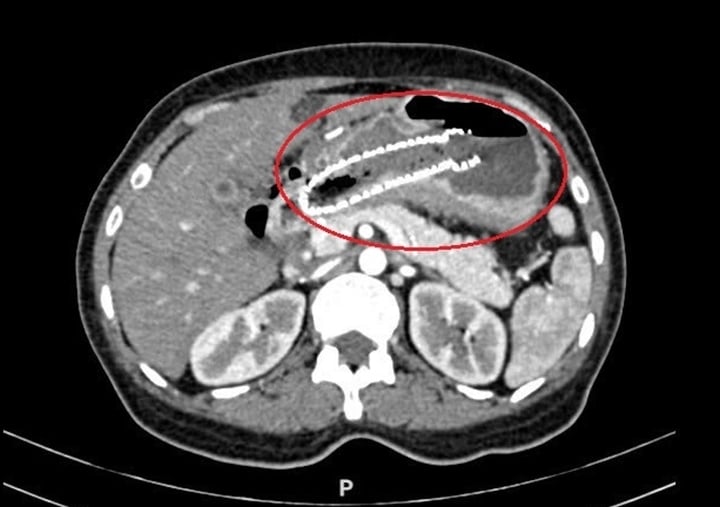

Ảnh chụp CT của chị Quyên cho thấy khối u dạ dày chèn ép tá tràng. (Ảnh: BVCC)

Trở lại Việt Nam, chị tuân thủ điều trị tại Bệnh viện Tâm Anh. Sau ba đợt truyền thuốc và đặt stent, các triệu chứng giảm rõ rệt, chị ăn uống tốt, CT cho thấy khối u giảm kích thước, không phát hiện thêm tổn thương mới.